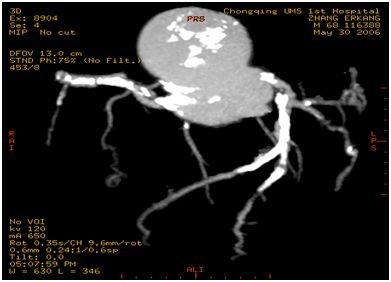

整个做的过程就是静脉注射碘造影剂后,CT机根据造影剂从注射至到达心脏血管不同部位的时间、按照预先设定的程序快速进行扫描成像,这个成像是把一支血管一个层面一个层面扫描出来的,也就相当于把一根血管截成一小段一小段成像,然后用计算机技术把这些影像重新组合(重建)起来,就可以看血管了。所以这个造影看到的图像,跟插导管造影看到的图像有所不同。